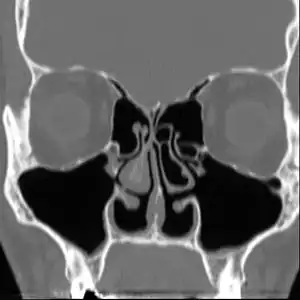

| Altered nasal anatomy after bilateral subtotal inferior turbinectomy | |